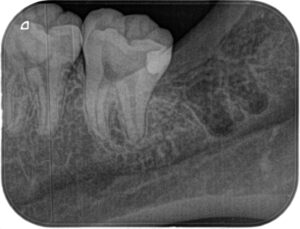

親知らずを抜いた後に小さいX線写真を撮ると第二大臼歯遠心に大きな虫歯がはっきりと写ってきました(下の赤い部分が虫歯です)

術後レントゲン撮影。虫歯をとったところのみをコンポジットレジンで詰めました(上の写真で白く写っている場所です)